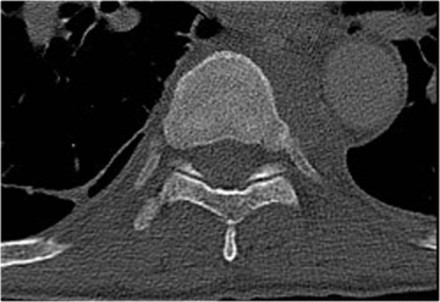

The x-ray of the C-spine in this patient was normal and did not show the fracture.

First look at the first CT-images and decide what is going on.

Then scroll to the next images.

In this case of translation there is bilateral facet dislocation and also a horizontal fracture of the spinous process.

There is severe narrowing of the spinal canal.

Continue with the MRI-images.

Again look at the first MR-images and decide what is going on.

Then scroll to the next images.

The findings are:

- Anterior displacement of C7 to Th1.

- Protrusion of the disc.

- Compression of the spinal cord.

- Bone marrow edema in several vertebral bodies, either due to contusion or fracture.

- Interspinous edema and disruption of the ligamenta flava C7-Th1 and supraspinous ligament Th1-Th2.

In some cases it can be difficult to decide whether there is a translation or distraction injury and we have to assume that the traumtic mechanism is a combination of forces.